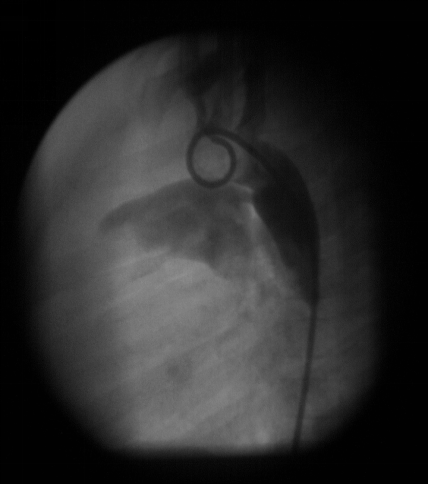

动脉导管未闭:心血管造影表现

△ 主动脉弓降部造影主动脉侧位显示PDA

△ 心血管造影已不是诊断PDA的常规方法

△ 在PDA封堵治疗时使用